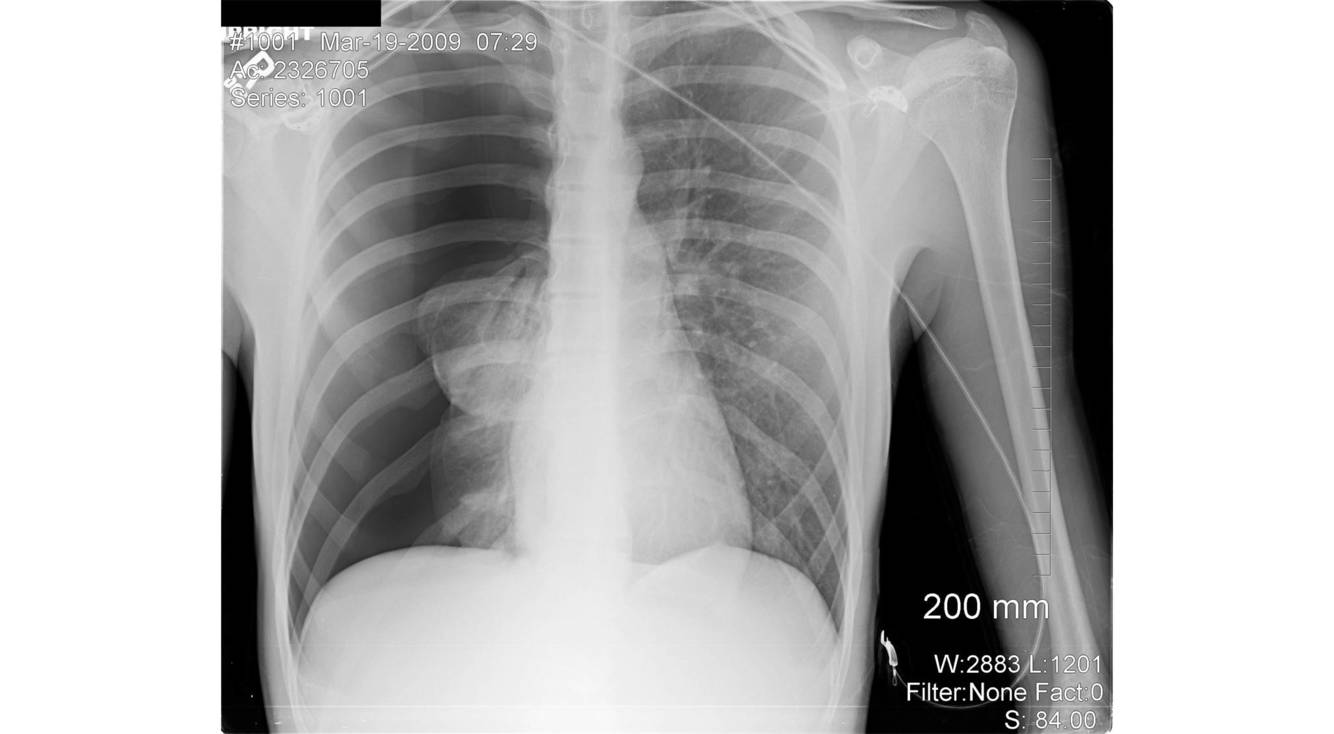

What is shown in in this image?

Pneumothorax